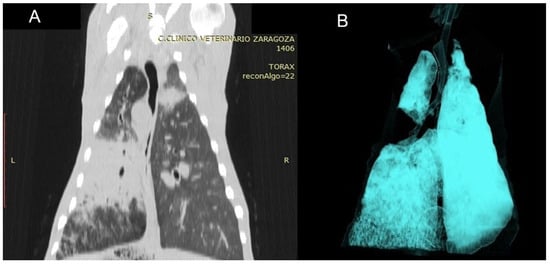

3.3.6. Ovine Pulmonary Adenocarcinoma (OPA)

| OPA | Primary masses with satellite nodules | −5 to −30 HU (primary), −90 to −200 HU (metastases) | Solid masses; differences in tissue composition between primary and metastatic lesions |